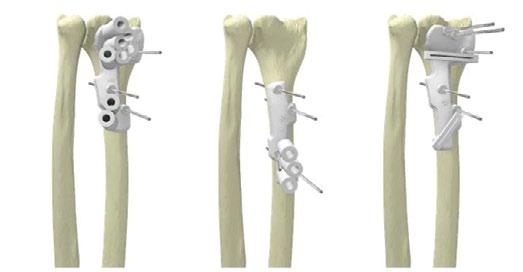

Earlier this year Materialise launched its latest personalised solution, the TRUMATCH® Personalised Shoulder system. With its expanded collaboration with DePuy Synthes, its US distributor, the new online platform and 3D printed guides for shoulder surgery was unveiled recently at the AAOS annual meeting in New Orleans.

The unique TRUMATCH® Personalised Solutions Shoulder System will help orthopaedic surgeons prepare for shoulder arthroplasty surgery, specifically addressing Reverse Shoulder Arthroplasty (RSA) and Anatomic Shoulder Arthroplasty (TSA) operations. It offers surgeons an all-in-one, web-based platform that allows them to better plan and prepare for these operations as well as to order patientspecific 3D-printed surgical guides.

RSA and TSA operations present unique challenges to surgeons with limited visibility as the result of the small incision, the Glenoid cavity being sited deep in the surgical window and the lack of reliable landmarks. However precise alignment is necessary, not just because of limited bone stock, but because of its impact on overall screw length and fixation (with RSA) and the occurrence of peg perforation (with TSA).